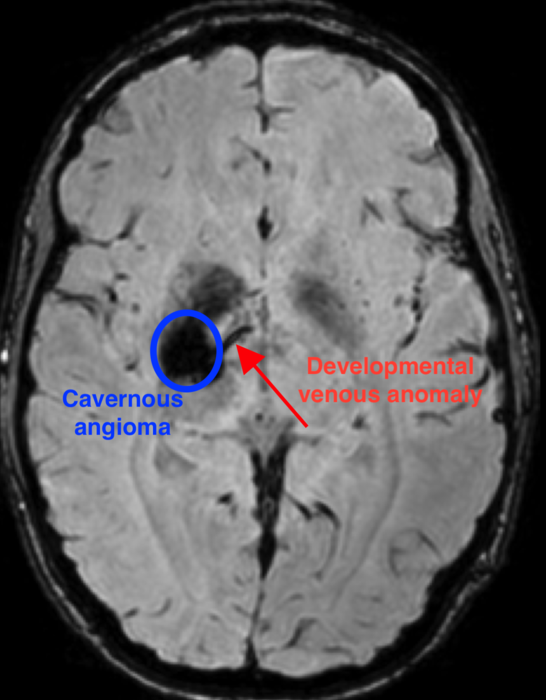

图像:海绵状血管瘤患者的MRI,显示血管瘤的位置和与之相连的发育性静脉异常

图片来源:Issam Awad医学博士提供。

这项新研究发现了一种独特的突变组合,它发生在大脑发育过程中,可导致海绵状血管瘤。首先,PIK3CA基因的突变导致了大脑血管的异常模式,即发育静脉异常,简称DVA。DVA本身一般是无害的。但是,当几个基因(如MAP3K3、KRIT1、CCM2或PDCD10)中的一个在异常静脉区域发生第二次突变时,就会形成海棠状血管瘤。